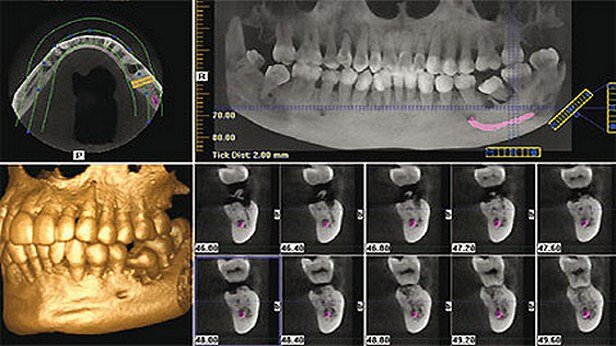

ДИАГНОСТИЧЕСКИЕ ВОЗМОЖНОСТИ КЛКТ ЧЕЛЮСТЕЙ (КТ ЧЕЛЮСТЕЙ) В ТЕРАПЕВТИЧЕСКОЙ СТОМАТОЛОГИИ АМБУЛАТОРНОЙ ПРАКТИКИ

На основании данных трехмерной дентальной объемной томографии были предложены новые алгоритмы диагностического обследования пациентов в стоматологии и сформированы показания для рентгенологического исследования пациентов с заболеваниями зубов и околоносовых пазух.

Использование данного метода позволяет мгновенно получить снимок зубов на экране монитора, оценить качество снимка челюстей и при необходимости повторить исследование, после чего произвести печать результатов исследования на принтере. Специальные методы обработки КЛКТ изображений дают возможность выделить и увеличить любые области снимка, изменить яркость, определить плотность тканей и измерить длину корневого канала. Применение цифровых методов рентгенодиагностики позволяет снизить лучевую нагрузку для пациентов. Совершенствование лечебных мероприятий в клинической стоматологии возможно только с улучшением уровня диагностики. Наиболее важная роль в ней отводится методу КЛКТ челюстей, КЛКТ челюсти, который, является важнейшим инструментом при постановке диагноза и планировании лечения. После проведения качественной диагностики повышается эффективность методов лечения и предотвращается потеря зубов.

КЛКТ зубов является ведущим методом как в первичной диагностике, так и для контроля отдаленных результатов лечения в стоматологической практике.